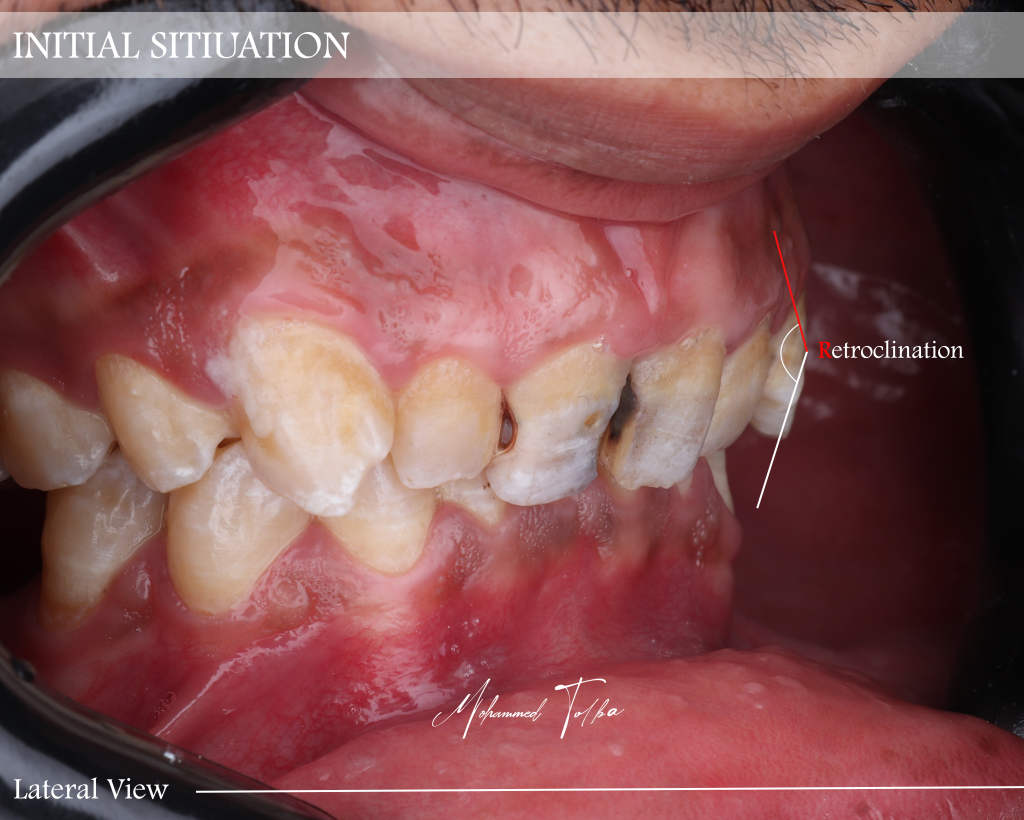

The patient had four anterior teeth retruded palatally, associated with a deep bite and bilateral posterior stoppers